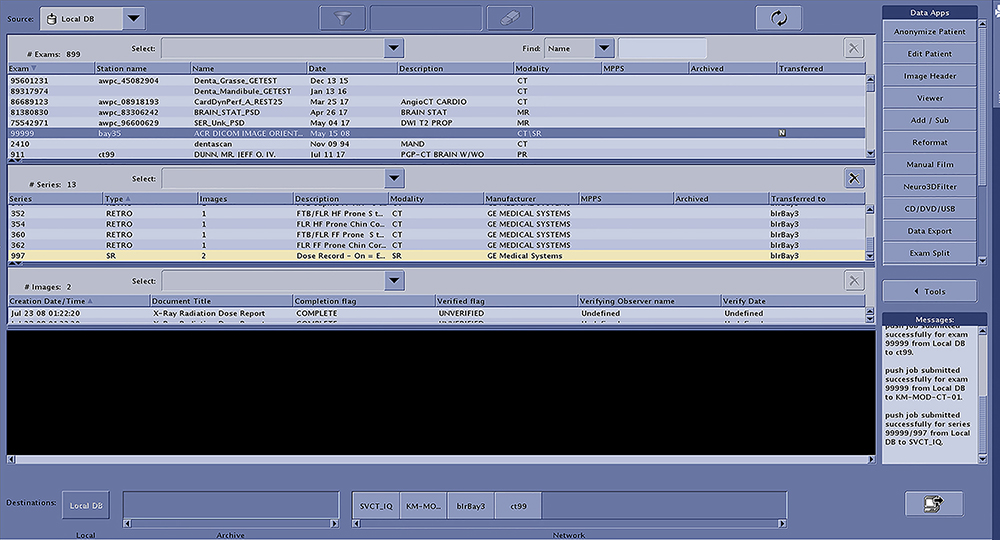

- Verify exam 99999 is listed in the Image Works browser. See Figure 1, “Select

Exam and Series to Transfer.”

- Patient Name = ACR DICOM IMAGE ORIENTATIONS

- Patient ID = FIELD TEST IMAGES DATA SET

note:If the exam does not exist, refer to Figure 2, “Reloading the Test Images,” for instructions..

- Identify the Hospital Review Station equipment that is to be evaluated. Your Customer will supply this information.

- Using the Image Works browser, add these Review Station destinations to the network remote host list. Add all destinations that will be evaluated.

- Using the Image Works browser, verify the connection to these Review Station destinations by using the Ping DICOM host menu selection. Ping all destinations of all Review Stations that will be evaluated.

- To demonstrate the capability of the Review Station equipment

to properly orientate the Flip / Rotate images, use the Image Works

browser to send Exam 99999 to the remote destination. See Figure 1, “Select

Exam and Series to Transfer.”note:

Series 997 can be ignored.

Figure 1. Select Exam and Series to Transfer